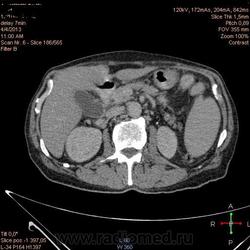

Здравствуйте, коллеги.Помогите разобраться.Пациент 1949 г беспокоять боли в животе , отсутствие аппетита, похудание .За неделю пожелтел, ослаблен.Нужно исключит кацер головки подж.железы.Анализы сегодня сдал еще не готовы.УЗИ зак увеличение л\узлов у ворот печени.Образов головки подж.железы ?На КТ жировой гепатоз.вроде головка подж железы не увеличены.

Мне надо исключить или поставить образование головки подж.железы.Хирурги ждут заключение, хотять оперировать.

Даже если вы пропустили малый рак панкреас, пациент умер не из-за него - желтуха не механическая, а, вероятней, паренхиматозная.